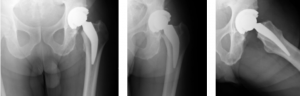

Case Report #3

Scott Dunitz, MD

Tulsa Bone and Joint Associates

A 63-year-old Caucasian female weighing 244lbs diagnosed with osteo/degenerative arthritis received Advita’s Alteon Neck Preserving stem with a Bioloxdelta femoral head and InteGrip acetabular shell. The patient went under spinal anesthesia using a direct anterior surgical approach with an incision size of 9cm. There was an estimated blood loss of 200cc and surgery duration was 80 minutes. The patient was discharged after one day postoperative with a walker to in home care for rehabilitation.

Pre-Op AP Pelvis

Harris Hip Score 31 (max=100) | Oxford Hip Score 9 (max=48)

6-Week Post-Op

Harris Hip Score 68 (max=100) | Oxford Hip Score 38 (max=48)

3-Month Post-Op

Harris Hip Score 84 (max=100) | Oxford Hip Score 37 (max=48)

1-Year Post-Op

Harris Hip Score 100 (max=100) | Oxford Hip Score 46 (max=48)

CONCLUSION

Pre-op, this patient presented with low Harris Hip and Oxford Hip scores. The direct anterior approach used in her surgery has been associated with faster functional recover than the posterolateral approach, and one-year post-op, her scores increased by more than 69.0 percent on the Harris Hip and 80.4 percent on the Oxford Hip. The patient is satisfied with her total hip replacement, and her surgical outcomes continue to be followed on an annual basis. •